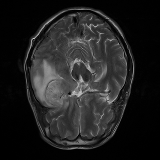

We obtain a subject-wise mean Dice score of 32.94% without any post-processing. By using a simple post-processing with erosion and dilation with filters, this number improves to 48.20% mean Dice score. In comparison, a similar study conducted by [3] consisting of a multitude of algorithms including AnoVAEGAN [4] and f-AnoGANS, obtained a best mean score of 27.8% Dice after post-processing by f-AnoGANS. Before post-processing the best method was Constrained AutoEncoder [8] with a score of 9.7% Dice. An exhaustive list is presented in Table 1. Figure 4 shows sample images of our results.

Brain Tumor Segmentation (BraTS 2019). In this task, we perform patient-wise two-fold cross-validation on the Brats-2019 training set. In each training fold, we use a 90/10 split after removing empty slices. The 2D slices from the 90% split without tumors are used to make our reference distribution ; while the 2D slices with tumors from the 90% split and all the slices from the 10% split are used for training our model. As a result, the sample size of for fold one and two amounts to 11,745 and 12,407 respectively, while the size of amounts to 11,364 and 10,786, respectively. We train this network using two cycles in the first stage and one cycle in the second stage.

We obtain a subject-wise mean Dice score of 63.67% for the brain tumor segmentation. Utilizing a simple post-processing scheme of erosion and dilation with filter, we improve our mean Dice score to 68.01%. Figure 4 shows samples generated by our ASC-Net and Table 2 shows our before and after post-processing results. We attempted to apply f-AnoGANs [34] by following their online instructions and failed to generate good reconstructions as shown in Figure 5. The failure of AnoGANs in the reconstruction brings to light the issue with the regeneration based methods and the complexity and stability of GAN-based image reconstruction.